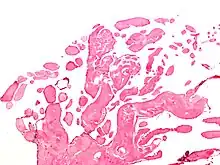

| Micrograph of a papillary fibroelastoma, a benign tumor of heart valves. H&E stain. | |

- Papillary fibroelastoma

A subset of the primary tumors of the heart are tumors that are found on the valves of the heart. Tumors that affect the valves of the heart are found in an equal distribution among the four heart valves.[2] The vast majority of these are papillary fibroelastomas. Primary tumors of the valves of the heart are more likely to occur in males. While most primary tumors of the valves of the heart are not malignant, they are more likely to have symptoms related to the valve, including neurologic symptoms and (in a few cases) sudden cardiac death.